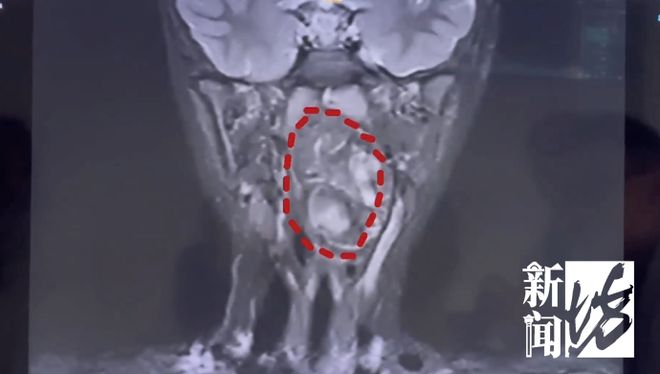

图为拍的CT片子

复旦大学附属儿科医院 耳鼻咽喉头颈外科副主任 陈超:我们可以看出它有脂肪,有软骨,这是一对双胞胎,一个是我们正常的人发育成的人,另外一个他可能残留在这个咽旁间隙里面,就发育成了这样的一个畸胎瘤。

复旦大学附属儿科医院 耳鼻咽喉头颈外科副主任 陈超:6岁男孩的口咽腔大概在8公分左右,这个孩子的肿瘤已经高达6公分多,整个气道已经完全被这个膨大的肿瘤占据了,只有一条黑颜色的线,这是它透气的空间,再让它继续膨胀下来,它首先出现的一个症状应该是呼吸道的梗阻窒息,会出现窒息致死的可能。

肿瘤紧贴颈内颈动脉,已明显将颈鞘压弯

雪上加霜的是,由于肿瘤紧贴颈内颈动脉,甚至明显将颈鞘压弯,手术的出血风险极高,这或许也是当地医院没有收治的原因。